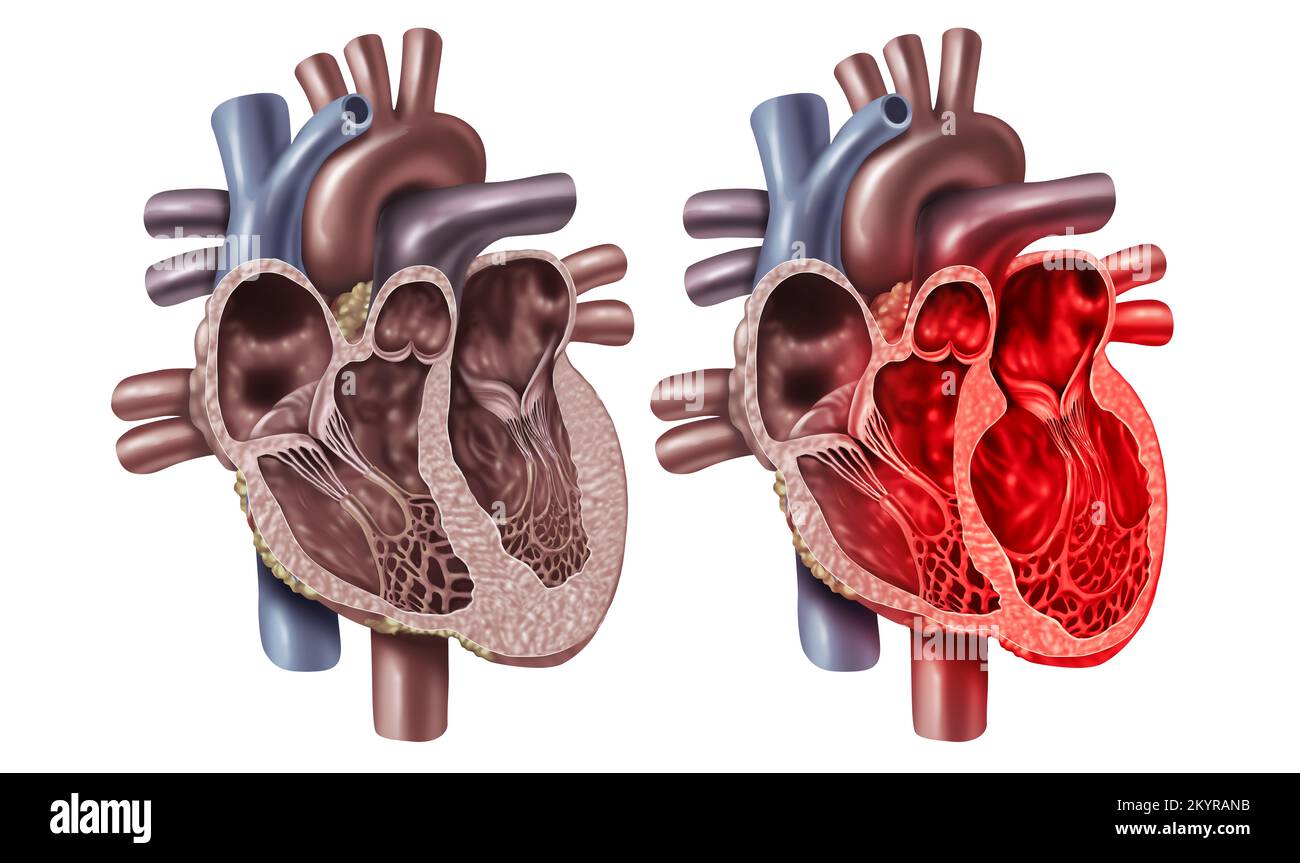

RF2KYRANB–Syndrome du coeur brisé ou cardiomyopathie Takotsupo avec un concept de section transversale d'anatomie d'organe sain d'un organe cardiovasculaire interne